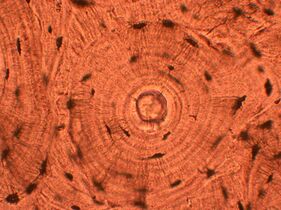

Whorled: Multiple concentric objects, or spiral-shaped

Cartwheel pattern: Center points that radiate cells or connective tissue outward